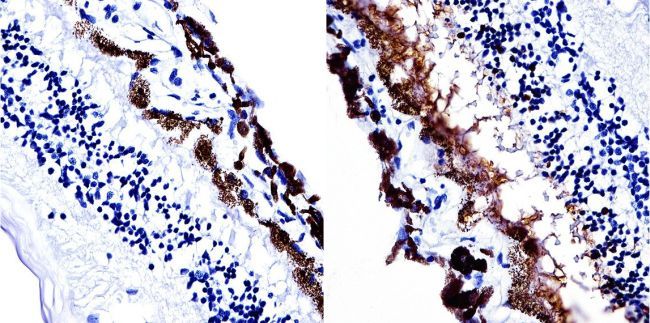

IHC-P analysis of human retina tissue using GTX15617 S-arrestin antibody [PDS1].

Antigen retrieval : 10mM sodium citrate followed by microwave treatment for 8-15 minutes.

Dilution : 1:20 overnight in a humidified chamber